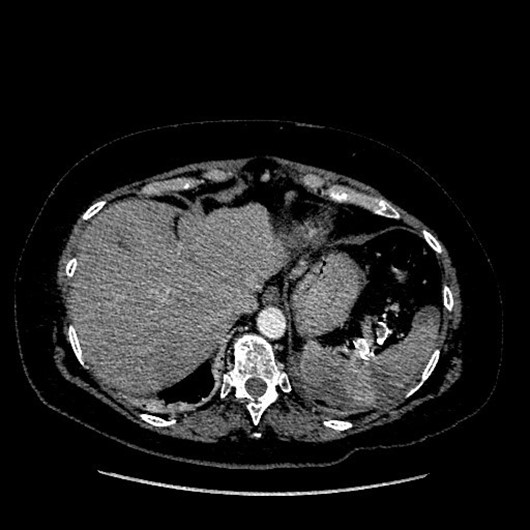

The incidence of hepatic and renal artery pseudoaneurysms was 28.2% and 23.1%, respectively. In cases with true aneurysms, it was observed that 87.3% of the lesions presented a saccular morphology, while 12.7% presented a fusiform morphology. In our patients, 18.8% of the cases had intrasaccular thrombosis, while the calcifications of the aneurysmal sac were demonstrated in 47.9%. The diagnosis of aneurysm was made in the asymptomatic phase in 68.2% of cases. In the asymptomatic phase, true aneurysms had an incidence of 84.8%, instead pseudoaneurysms 20.5% only. In patients with true aneurysm, the symptom most frequently found is abdominal pain in 8% of cases and active bleeding in 1.8%. Instead, in patients with false aneurysms, the most frequent symptoms were anemia in 30.8% of cases and active bleeding in 12.8%. In our study, sixteen patients were treated in the rupture phase. In figure 1 we reported a preoperative CT angiography of a hepatic artery aneurysm showing rupture of the aneurysmal sac.

Figure 1: Preoperative CT angiography of a hepatic artery aneurysm showing rupture of the aneurysmal sac.